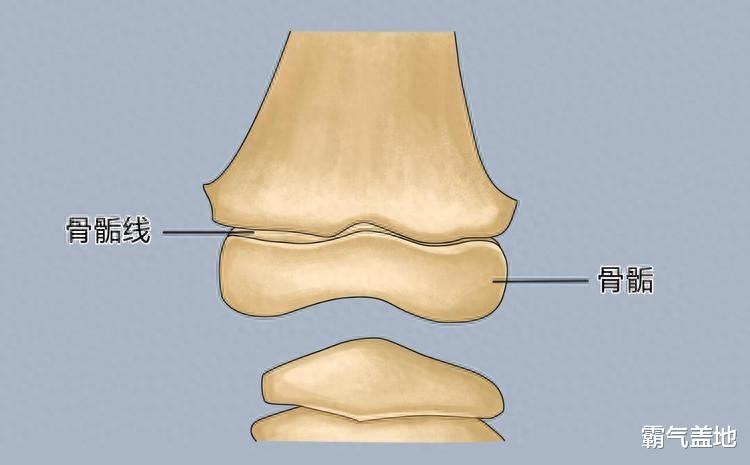

骨骺线:身高增长的“生命线”

骨骺线到底是个啥?简单来说,它位于我们长骨的两端,决定了孩子还能不能继续往上“窜一窜”。 想想建造房子,骨骺线就像是建筑工地上辛勤的工人,在生长激素的指挥下,不停地增殖、钙化,一点一点地把骨头拉长。